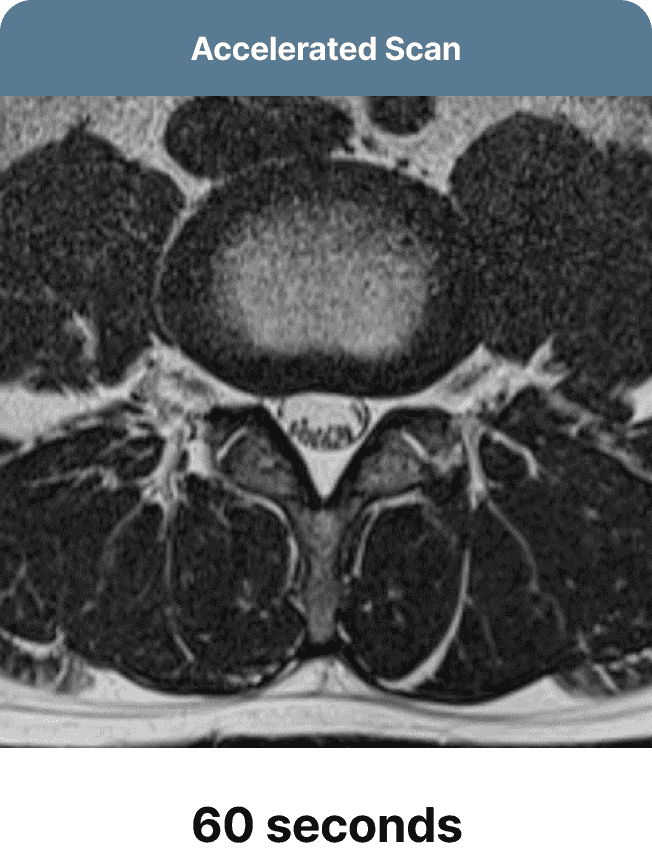

Our team will optimize MRI protocols to accelerate scans, initially producing faster yet low-quality images. SwiftMR's deep learning model is then employed to enhance the accelerated scans, effectively transforming them into high-quality images.